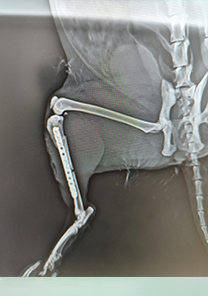

Tayfun Bey'in Kedisi Minnoş

Tayfun Bey'in kedisi Minnoş'un femur distalinde parçalı bir kırık tespit edilmiştir. Operasyon günü itibarıyla MN - HUND&KATT kullanılmıştır. Operasyonun üçüncü gününden itibaren kırıkla ilgili ağrı semptomları tamamen kaybolmuş ve Minnoş rahatlıkla yürümeye başlamıştır. Operasyondan 10 gün sonra kaynamalar başlamış ve remodalizasyona geçmiştir.